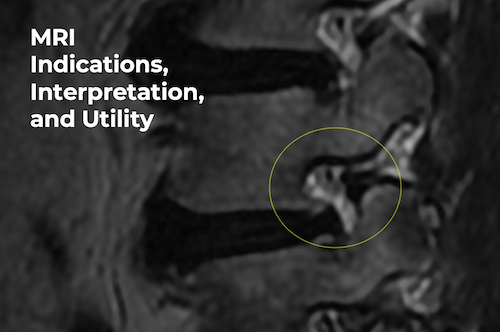

MRI Indications, Interpretation, and Utility

- This course is a recording of a live Zoom discussion about the indications, interpretation, and utility of spinal MRI in chiropractic practice.

- A focused chiropractic discussion related to indications, interpretation, and clinical usefulness of spinal MRI studies in chiropractic practice. Emphasis will be placed on appropriateness criteria, evidence-based reasoning and practical utility.